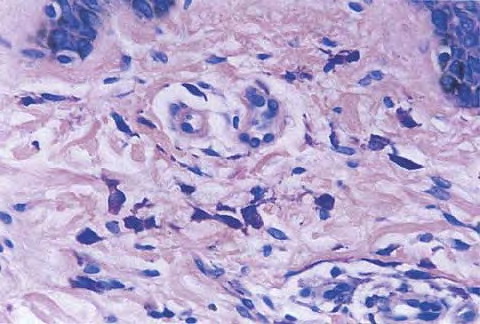

Adult mast cell disease (telangiectasia macularis eruptive perstans) =داء الخلايا البدينة عند البالغين